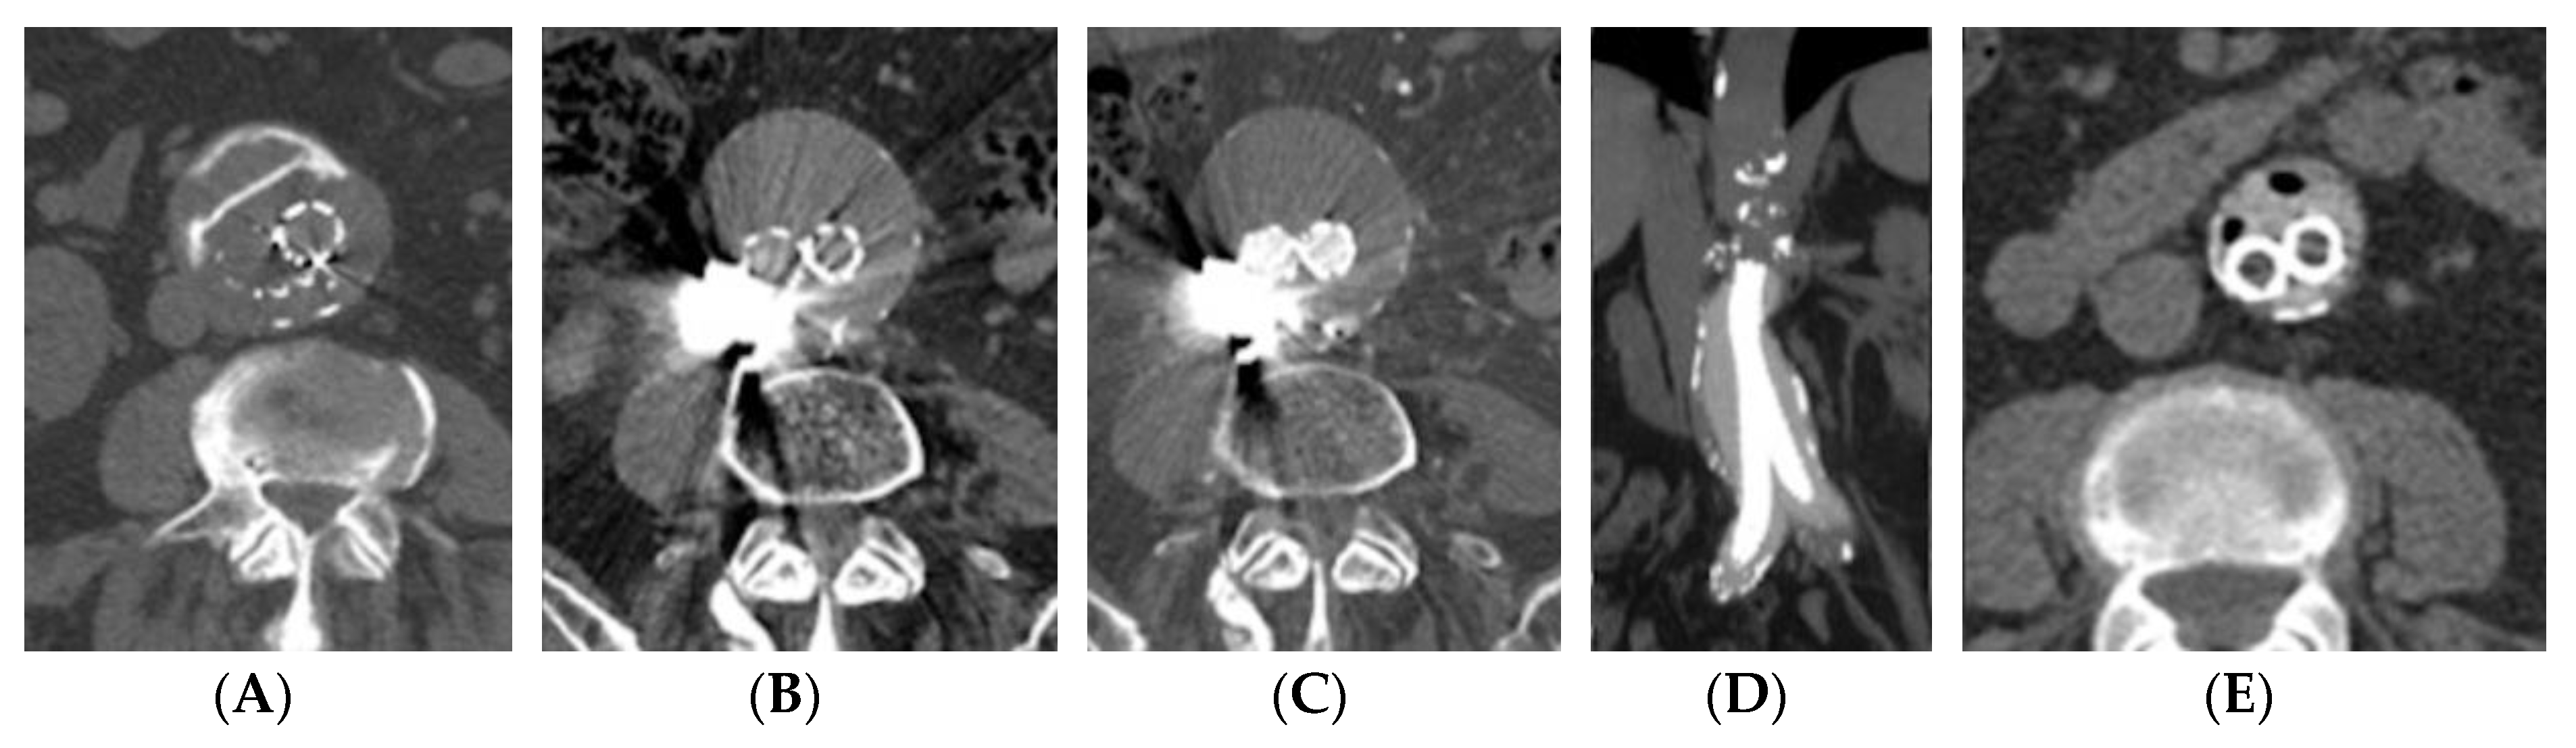

3.2. Computed Tomography (CT)—CT–Angiography (CTA)